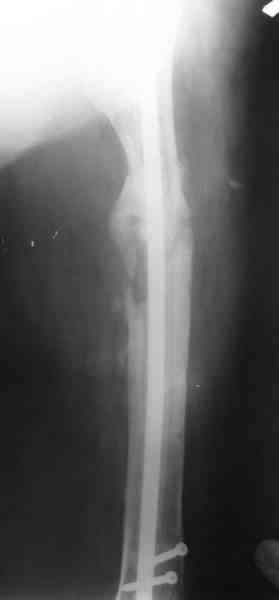

1, 2, 3, 4 - рентгенограммы бедра от 8 августа этого года (через четыре месяца после операции);

В качестве демонстрации лечения канального остеомиелита бедренной кости представляем пациентку (см. parts 2 и 3), которая как раз сегодня была у нас на контрольном осмотре. В мае этого года мы произвели ей фиксацию бедренной кости штифтом-спейсером по поводу ложного сустава и канального остеомиелита бедренной кости. Через 4 недели после операции свищи закрылись. Сейчас она ходит с полной нагрузкой на конечность.

4, 5, 6 - рентгенограммы бедра и фотографии пациентки (прошу прощения за низкое качество рентгеновских снимков) от 7 сентября 2007 г.